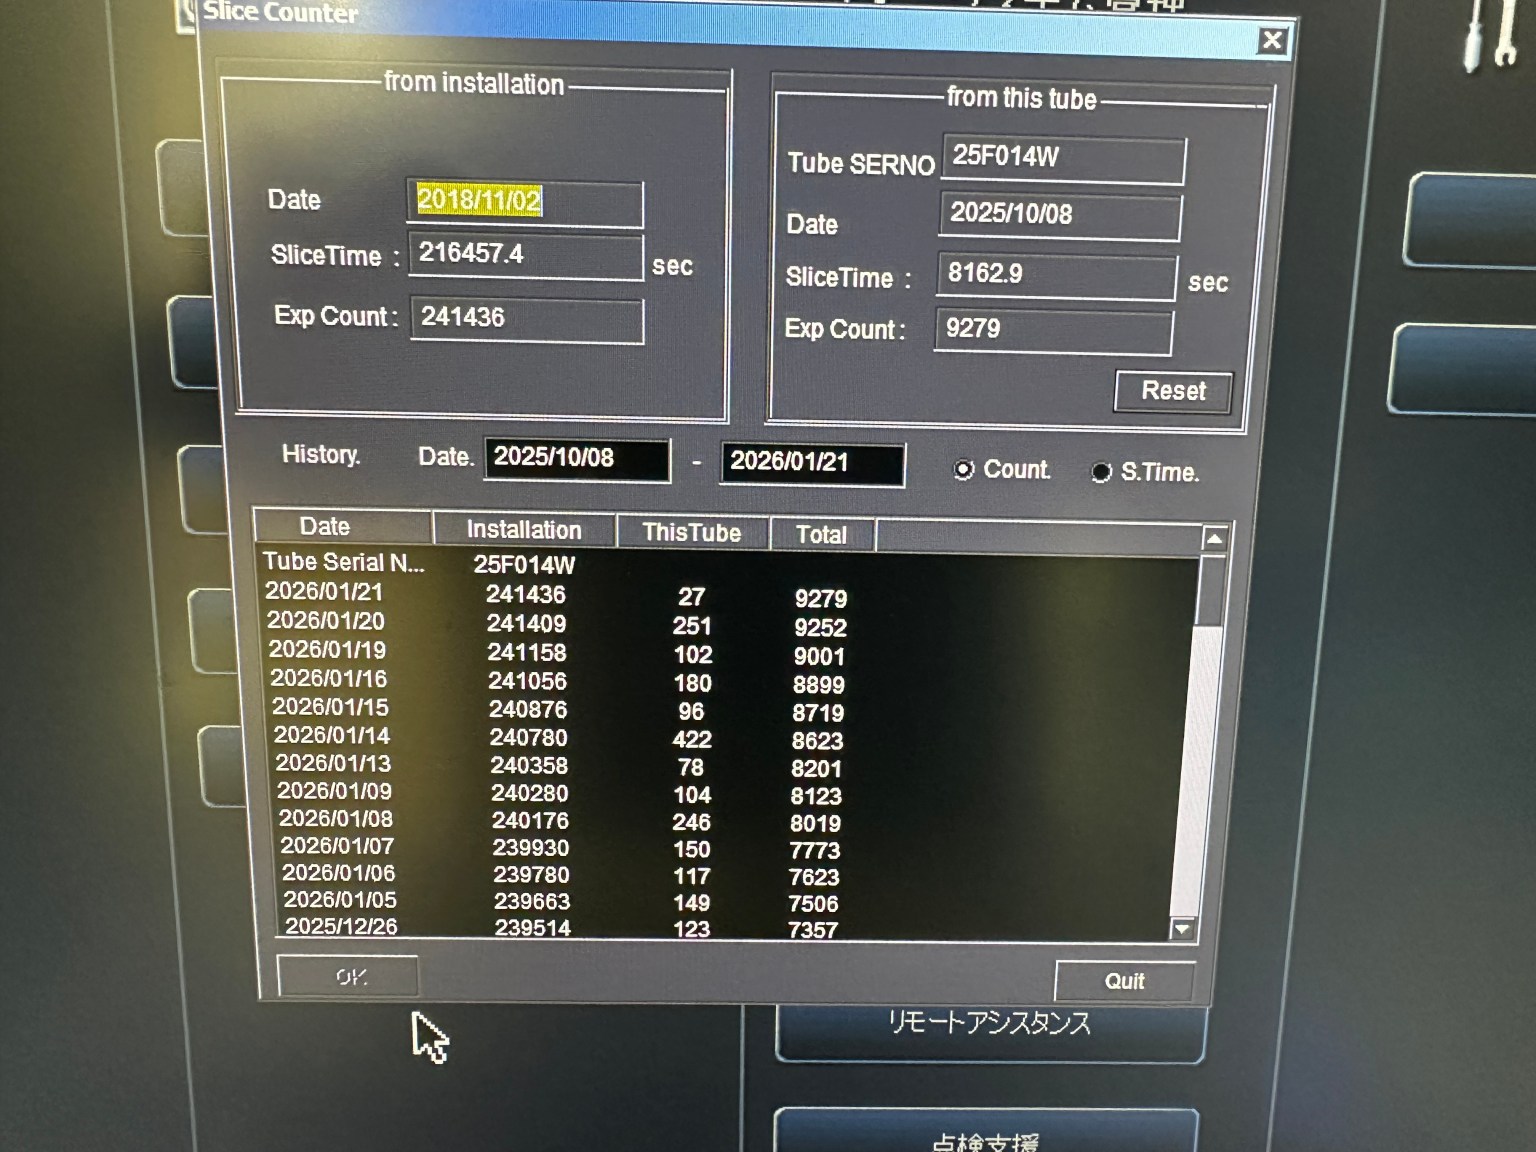

| Manufactured | : | November 2018 |

| Tube Manufactured | : | June 2025 (Almost new tube) |

| Tube Replaced | : | October 2025 |

| Tube Slice Time | : | 9779 sec |

| Tube Exposure Count | : | 11,157 |